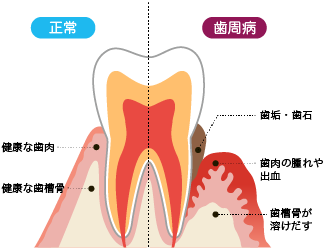

歯並びは歯周病の原因になるの?